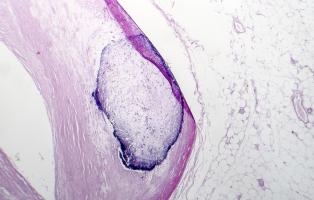

ATHÉROSCLÉROSE : Des nanoplastiques à côté de la plaque

Actualité publiée le 21/11/2024ATHÉROSCLÉROSE : Des caractéristiques cliniques cancéreuses ?

ATHÉROSCLÉROSE : Réaliser les promesses des sphingolipides

ATHÉROSCLÉROSE : La plaque plus tardive mais plus nocive chez les femmes ménopausées

ATHÉROSCLÉROSE : Mais comment stabiliser la plaque ?